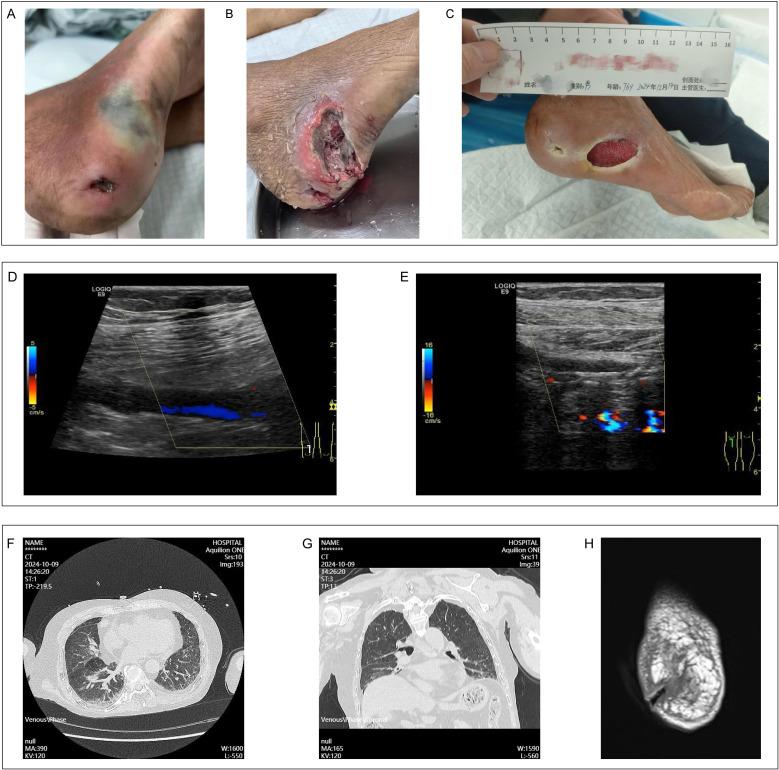

is an infrequently encountered Gram-negative bacterium capable of infecting humans and, in severe instances, precipitating sepsis. Presently, three species within the genus have been identified, with being the sole species implicated in human infections. To date, there has been only one documented case of human infection with in China. In this study, we present an additional case of human infection with a species. Notably, through 16S rRNA gene sequencing and whole-genome sequencing, the strain was identified as an unclassified species closely related to DSM 18708.

是一种罕见的革兰氏阴性菌,能够感染人类,在严重情况下会引发败血症。目前,该属内已鉴定出三个物种,其中 是唯一涉及人类感染的物种。迄今为止,中国仅有一例记录在案的人类感染 病例。在本研究中,我们报告了另一例人类感染该 物种的病例。值得注意的是,通过 16S rRNA 基因测序和全基因组测序,该菌株被鉴定为与 DSM 18708 密切相关的一个未分类物种。